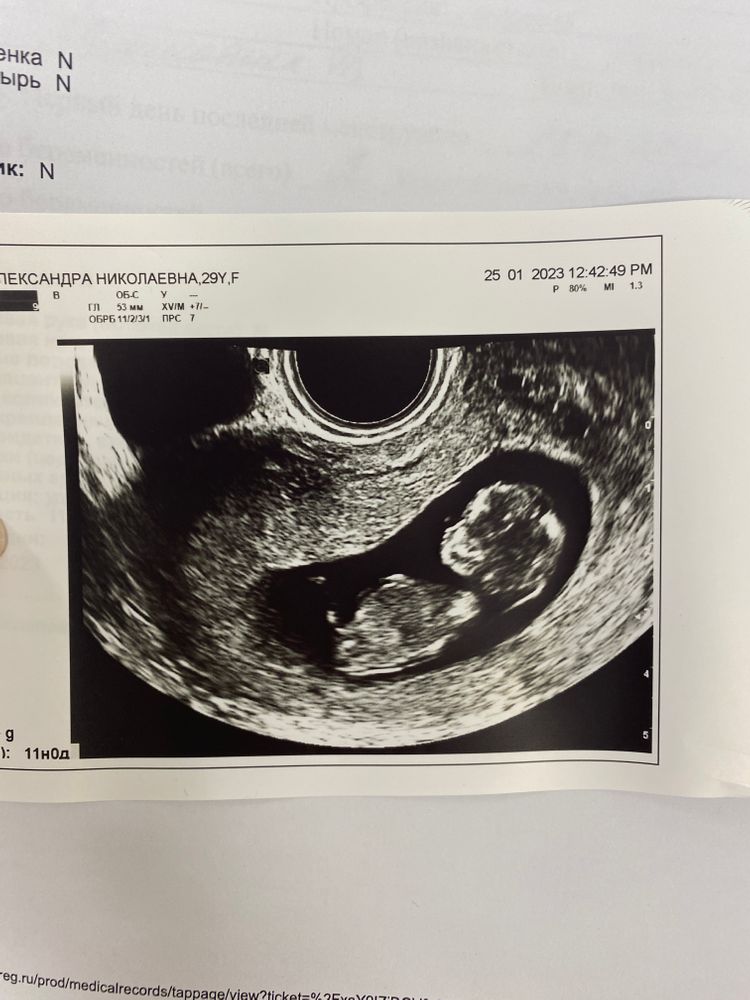

Скрининг был назначен на сегодня, на срок 11 недель ровно.

По моей креветочке… Креветочка уже превратилась в человечка, КТР 45 мм. ЧСС 156 у/мин. ТВП 1,4 мм. Носик визуализируется. Плацента по передней стенке. Малыш соответствует сроку 11,2.